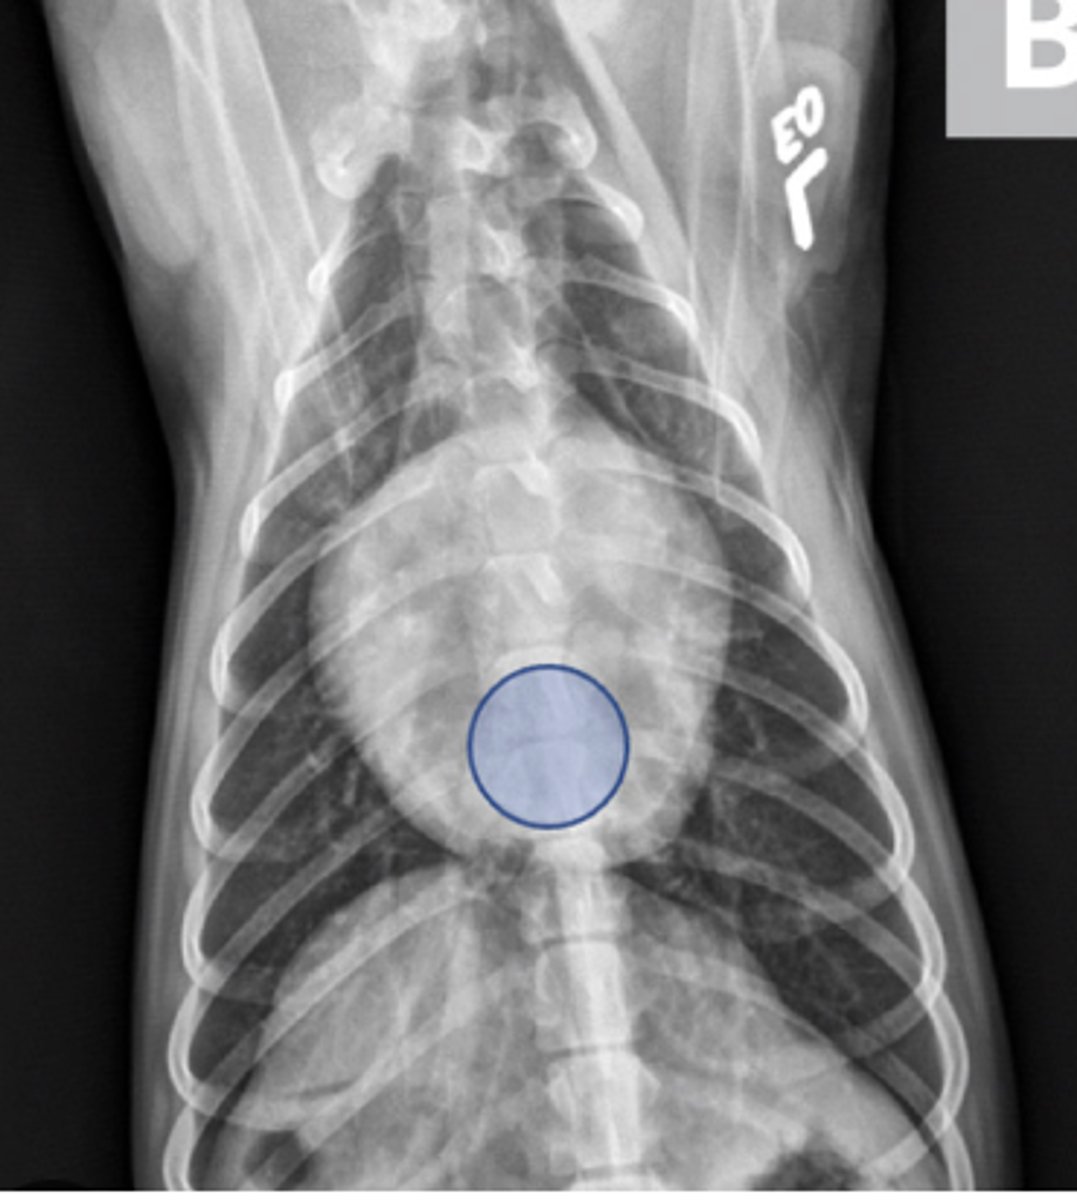

Free fluid

Radiograph; can't see much in abdomen - why?